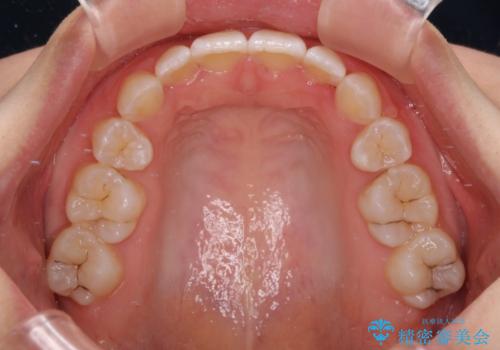

- 上下前歯のデコボコを気にして来院された患者様です。

口元の突出感はあまりなかったものの、デコボコを非抜歯で改善すると出っ歯になる可能性があるため、上下左右の第一小臼歯4本を抜歯し、ワイヤー装置にて矯正治療を行うこととしました。

口元の突出感がない分、奥歯を前方に移動させる必要がありましたが、予定の2年間で無事に治療を終えることができました。